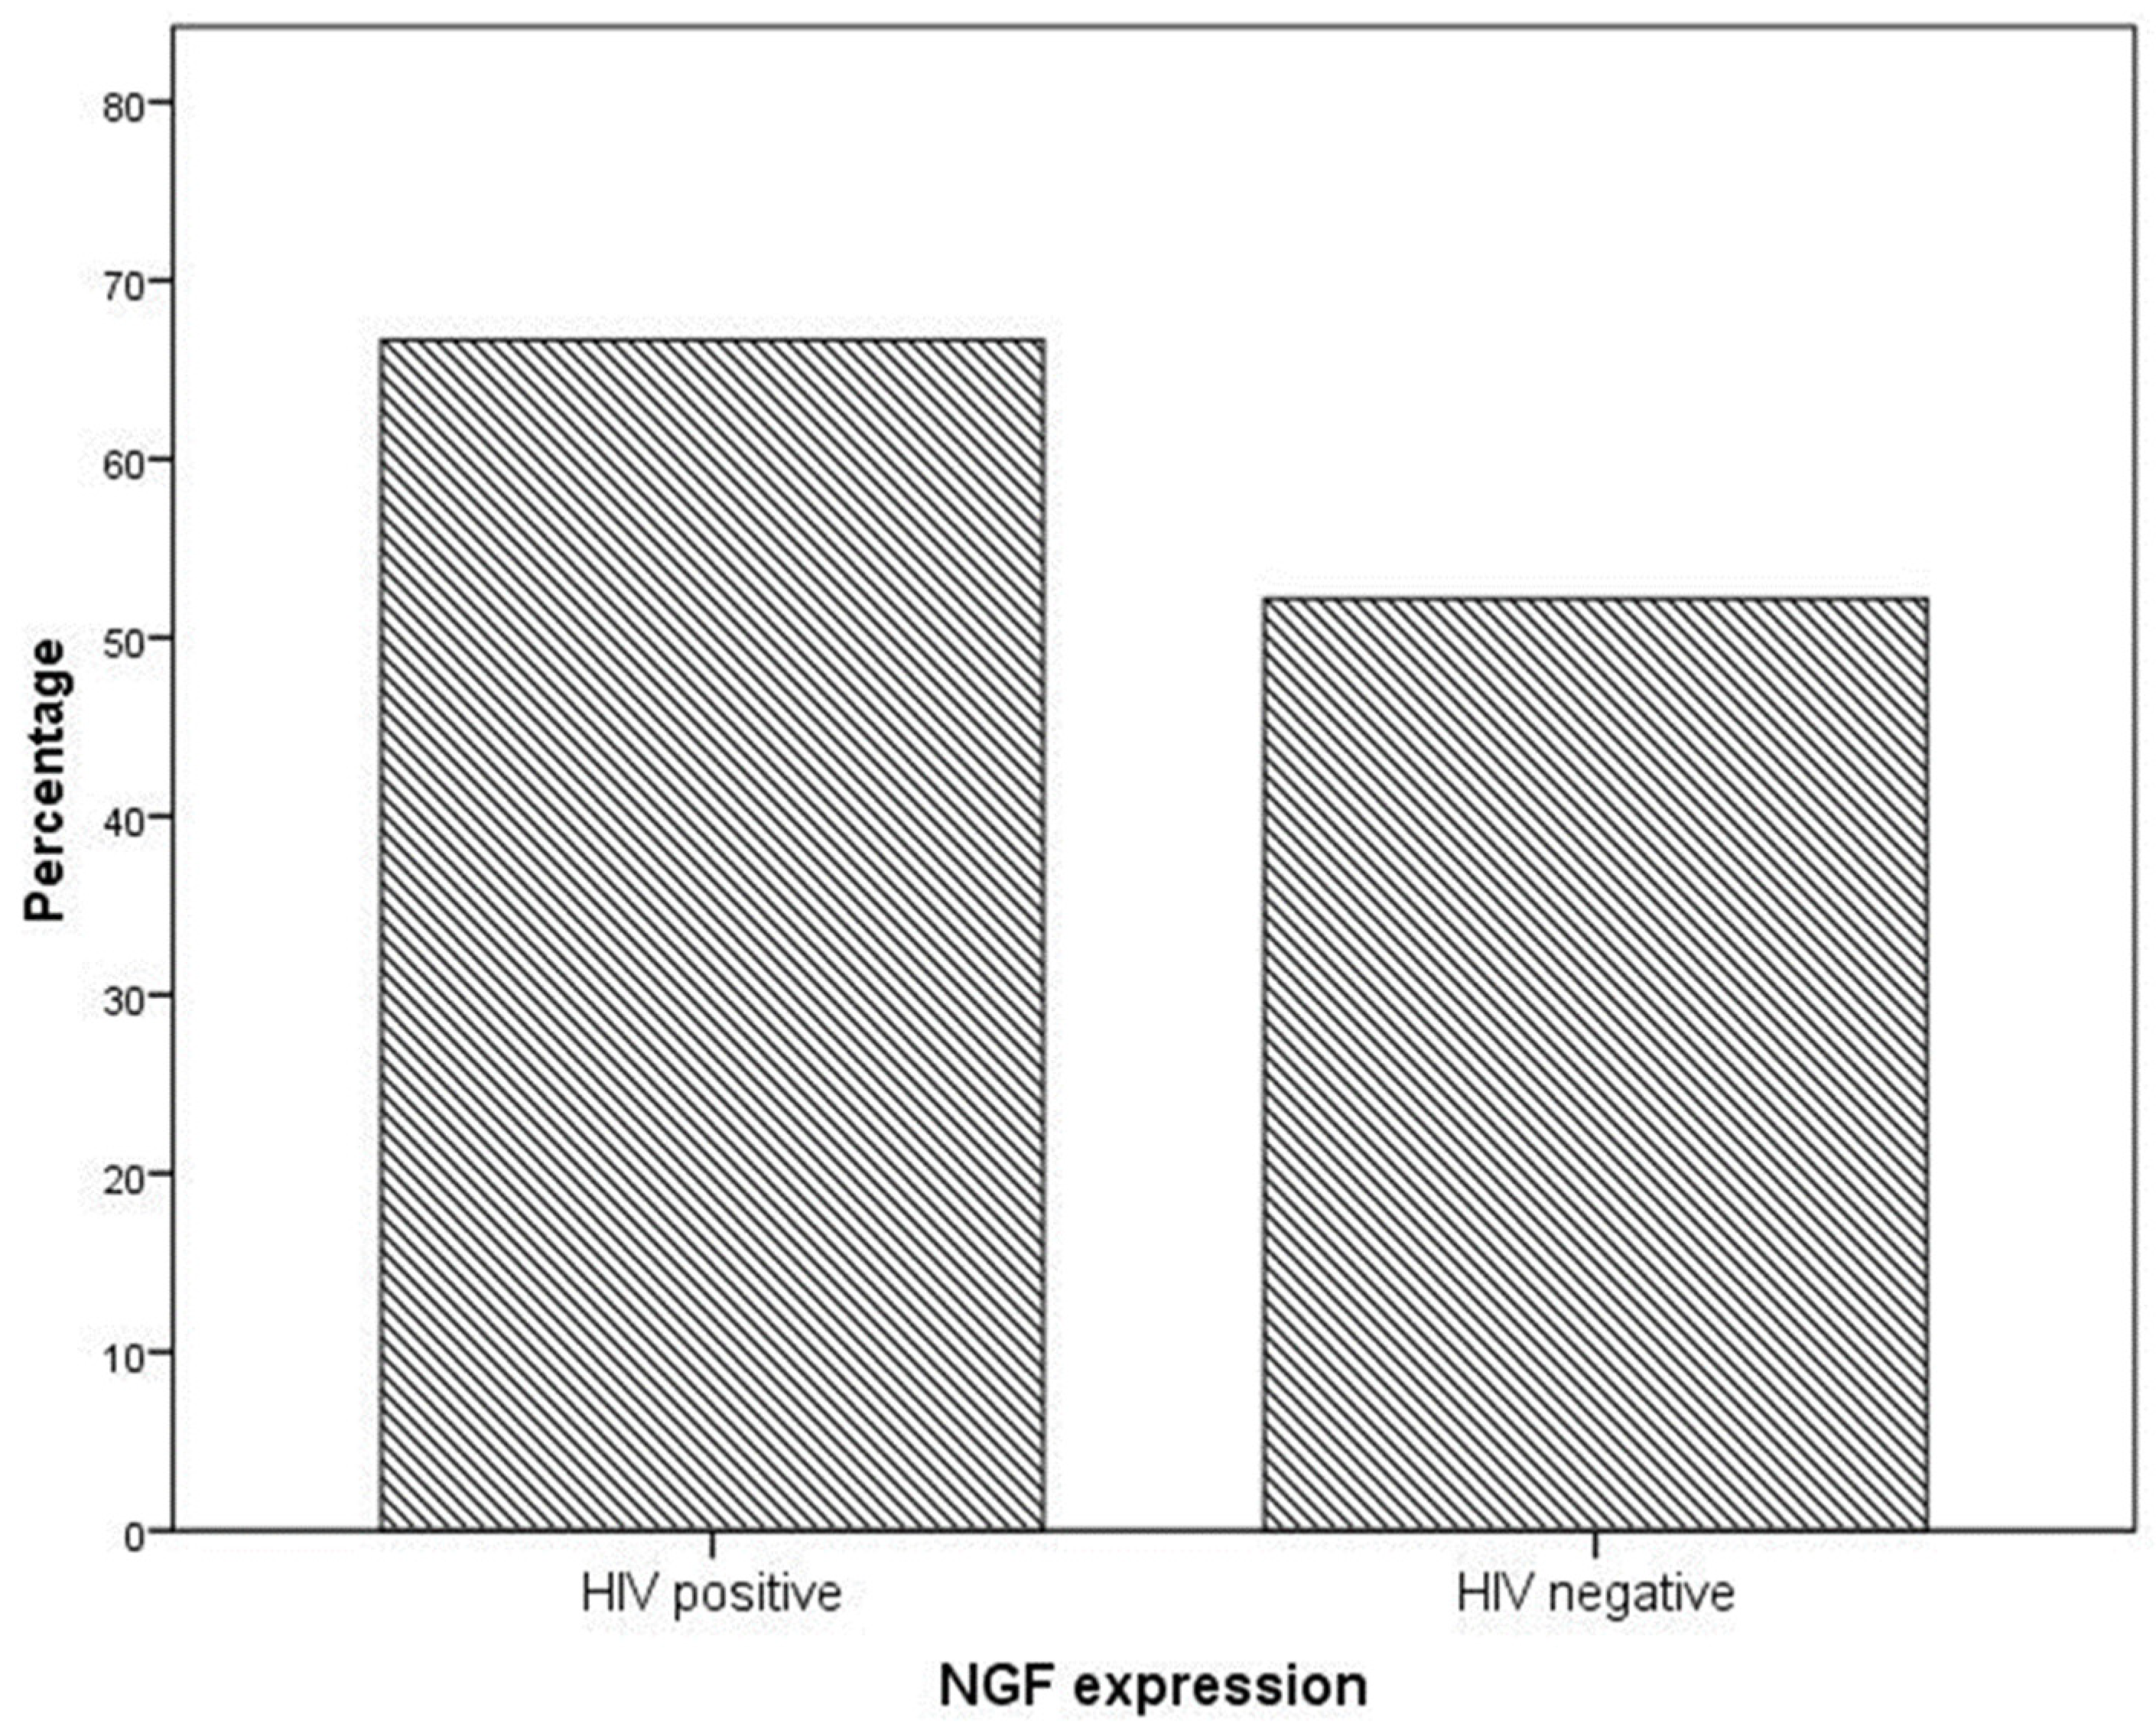

2. Results

4.1. Neurotrophin Expression in Cervical Dysplastic and Neoplastic Lesions